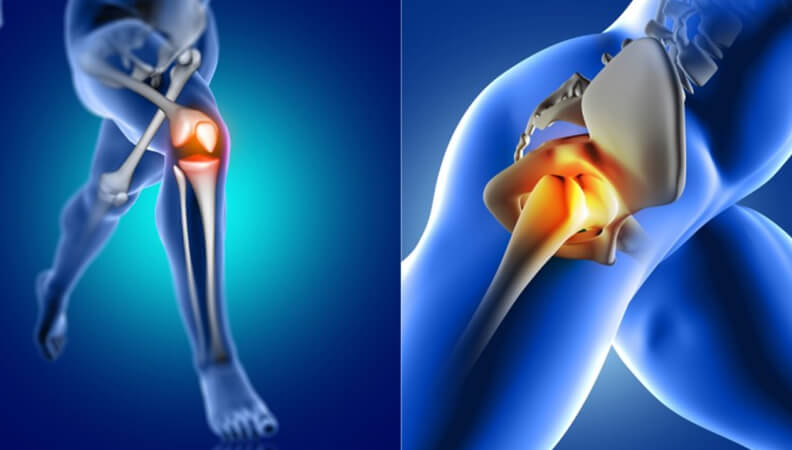

We offer advanced joint replacement procedures for hips, knees, shoulders, and other joints, utilizing latest technology and techniques to ensure optimal outcomes and faster recovery times.